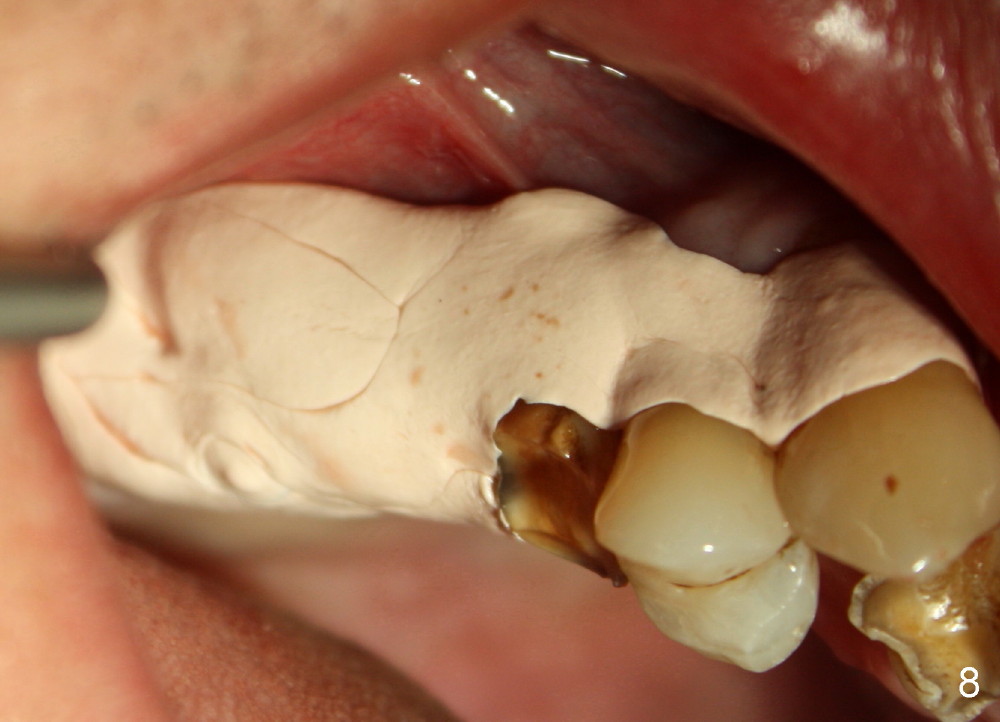

The flaps do not completely contact the implant when they are sutured. The wound needs protection during the initial postop stage. One of modes is to use perio dressing. The latter is not retentive in the distal edentulous area. Addition of a short abutment (Fig.7 A) over the implant should increase the retention of perio dressing (Fig.8) while micromovement of the implant is minimal. The tooth #30 is missing. There is no bone resorption 2 years 11 months post cementation (Fig.9).